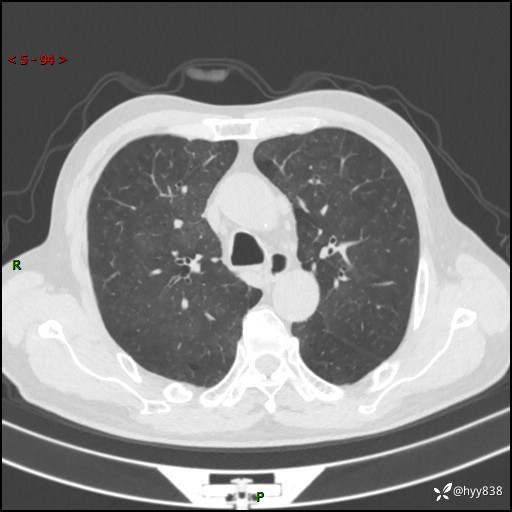

儿女怕老人寂寞,养了两只鹦鹉,呼吸科主任问我典不典型---结果公布~

武医生 等 4 位达人已点赞患者性别:男

患者年龄:71岁

主诉:喘气半年余,咳嗽乏力伴味觉减退2月余

简要病史:者半年前左右无明显诱因出现呼吸困难,轻微运动后出现喘气,未予以重视。2月余前受凉感冒后出现咳嗽,咳白色泡沫痰,不易咳出,于当地医院行输液治疗,未见明显好转,并感觉全身乏力,体力下降,并感口苦,味觉减退。近10余天前感咳嗽喘气加重,咳白色泡沫痰,不易咳出,口苦,味觉减退加重。为进一步检查及治疗,入我院就诊,门诊以“呼吸困难”收入院治疗。 起病以来,患者精神,睡眠,饮食欠佳,大小便可,体力下降明显,体重稍下降。

辅助检查:CT

临床诊断:呼吸困难

讨论:诊断?

胸部CT平扫